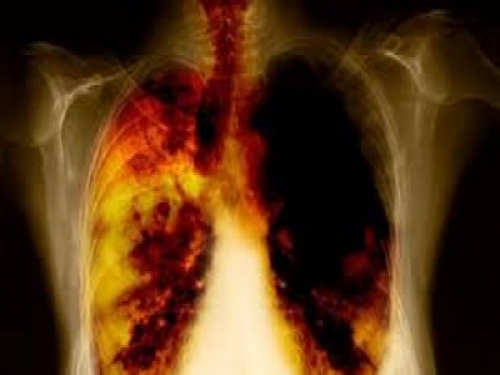

對抗肺癌,你必須知道的放療策略與進展!!!

早期肺癌常常無明顯症狀,發現肺癌的第一步,往往是體檢發現肺結節

就像打仗要先偵查一樣,出現肺結節,我們首先要先探清敵情,然後才能制定作戰方案。王教授首先講解了發現肺結節後的三大經典問題:是肺癌嗎?是哪種型別的肺癌?病變達到什麼程度?

回答這些問題,我們需要組織學診斷,並運用多種影像學檢查。只有準確的診斷,治療才會有的放矢,從而避免不必要的經濟、醫療資源的浪費以及耽誤病情。